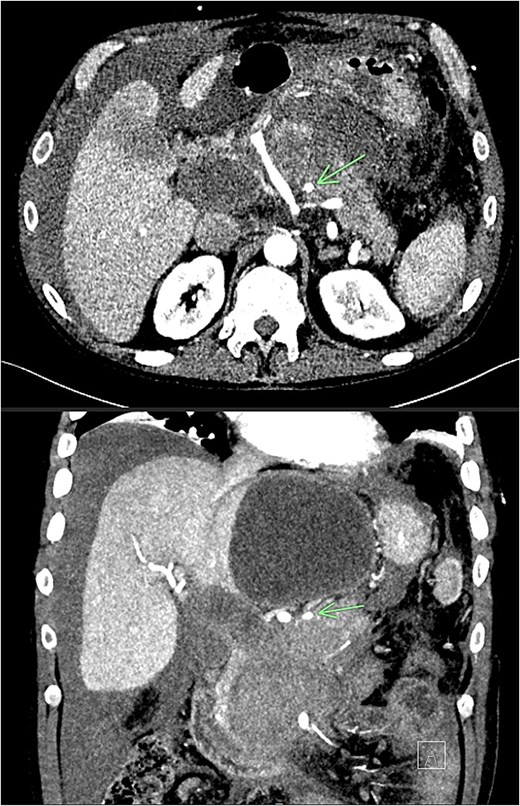

Despite the absence of abdominal symptoms, a computed tomography of the abdomen and pelvis (CTAP) was performed due to markedly elevated lipase levels. The CTAP (Figs 3–5) revealed evidence of acute pancreatitis (Fig. 5, arrow), with a complex peripancreatic fluid collection (Fig. 3, arrow). Additionally, a focal thrombus was observed within the portal venous confluence (Fig. 4, arrow). Further ultrasound of the gallbladder was negative for gallstones (Fig. 6), ruling out gallstone-induced pancreatitis.

CTAP coronal view; complex peripancreatic fluid collection (arrow) with extension behind the splenic vein to lie adjacent to the pancreatic neck and uncinate process.

CTAP coronal view; focal thrombus within the portal venous confluence (arrow).